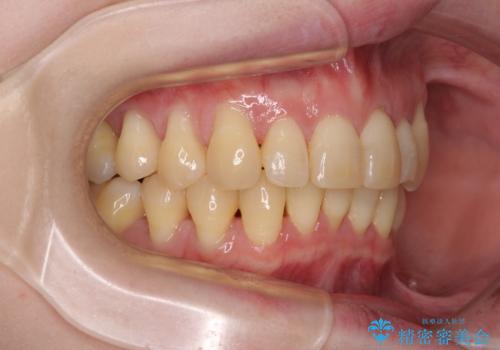

八重歯と先天欠損の歯列 ワイヤー矯正ですっきりと

- 八重歯と正中のズレを気にして来院された患者様です。

上顎左側が八重歯になっており、上顎正中が左側にずれていました。

下顎前歯が1本欠損していたため、上下正中の位置が合わせるという目標はなく、鼻筋に上顎正中を合わせていくように移動を行いました。